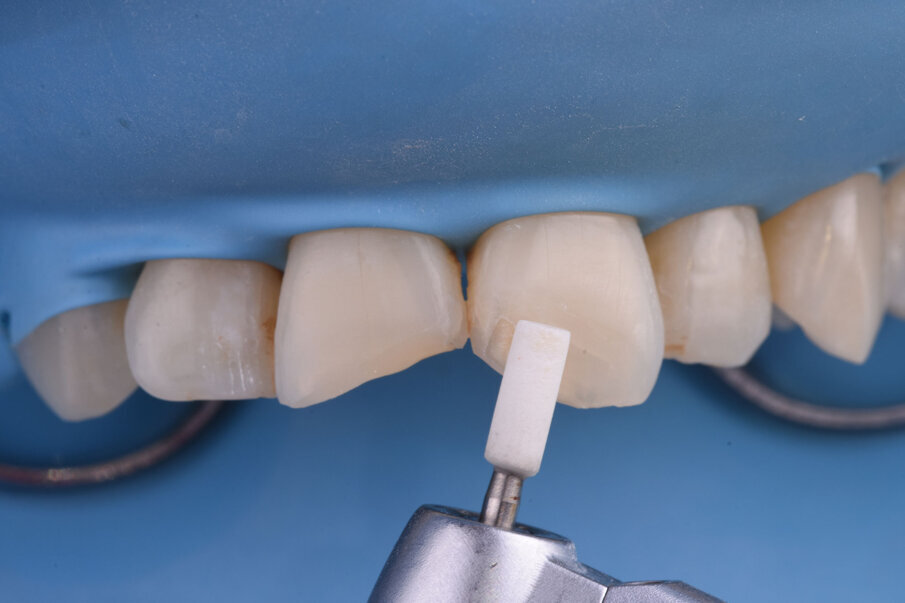

Sl. 11: Uklanjanje viška dentinske mase i obezbeđivanje prostora za gleđnu masu